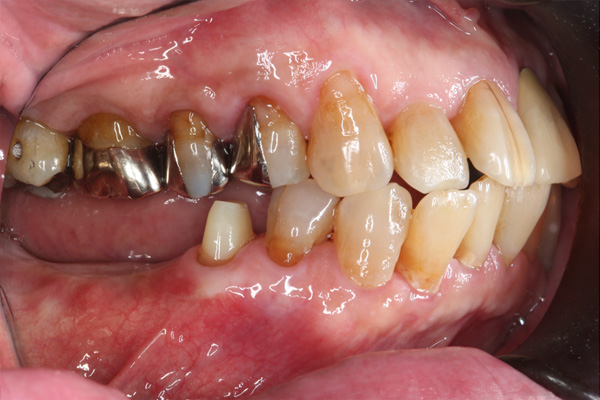

| 年代・性別 | 50代 男性 |

|---|---|

| 主訴 | 右上下の歯が痛い |

| 治療期間 | 約12ヶ月 |

| 費用 | 2,500,000円 |

| 治療内容 | インプラント、骨造成、結合組織移植、セラミック修復 |

| 治療に伴うリスク | インプラント周囲炎 セラミックの破折、脱離 |